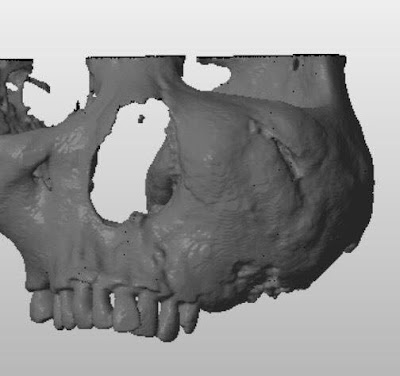

Use of proximal tibia as a donor site has been applied in jawbone reconstruction since the 1990s. Catone and colleagues described a U-shaped incision made on the iliotibial tract during tibial cancellous bone procurement for maxillofacial reconstruction in 1992. We used a curvilinear incision on the iliotibial tract in lateral approach in our tibial

cancellous bone harvesting procedure.

Eighty consecutive jawbone reconstructions utilizing autogenous tibial cancellous bone grafts in 78 patients from March 1998 through March 2008 were reviewed. The patient group consisted of 45 males and 33 females, ages 18 to 76 (average age 36.1 1 12.3).Minimal postoperative follow-up period was 3 months. Unlike the traditional U-shaped trapdoor incision on the iliotibial tract, our curvilinear incision was made almost parallel to the fibers of that tract.

Only mild complications were observed at donor sites, including temporary paresthesia, gait disturbance, and an unpleasant scar. The average procured graft volume was 17.8 mL. We also present the first case of reconstruction of mandibular continuity defects of up to 6 to 7 cm lengthwise by tibial cancellous bone grafting, which has not previously been reported in the English literature.